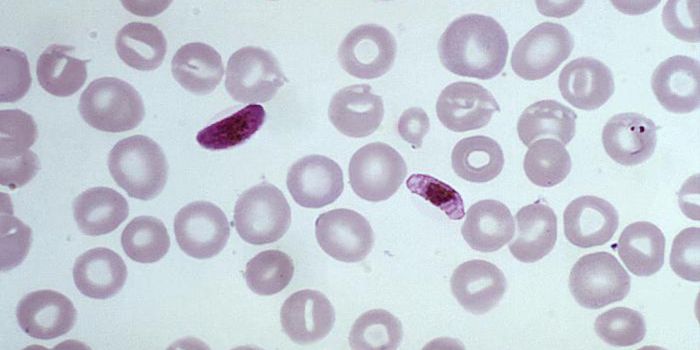

MAR 08, 2016CardiologyMalaria killed about 440,000 people—mostly young children—last year, but a new drug candidate may help fight ...